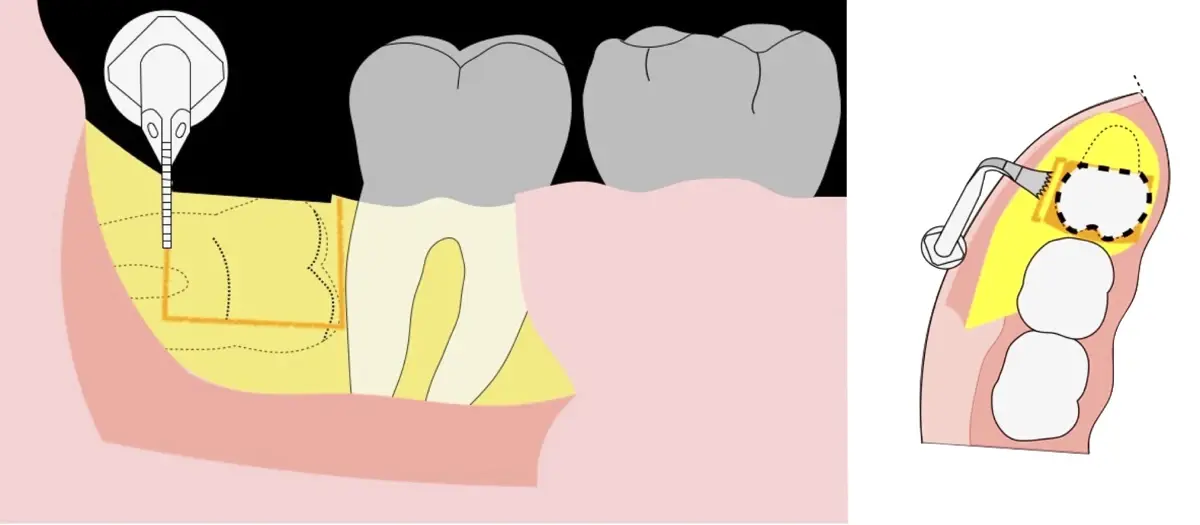

Figura 4. Demarcación de la zona de osteotomía con insertos de corte recto y/o angulado a nivel oclusal. Vista frontal (a). Vista oclusal (b).

Figura 5. Fractura y eliminación oclusal del fragmento óseo de la porción coronal oclusal.

Figura 6. Demarcación y fractura de la zona de osteotomía a nivel vestibular con inserto aserrado recto y/o angulado.

Figura 7. Eliminación del fragmento vestibular.